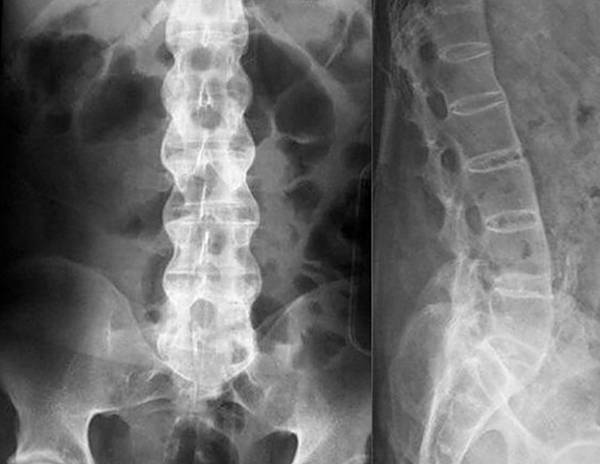

Если симптомы явно указывают на грыжу, остеохондроз или радикулит, для диагностики обычно применяют рентгенологическое исследование. Рентгенография относится к самым простым и доступным способам, к тому же, для снимка требуется совсем немного времени, в отличие от КТ, где пациент должен сохранять неподвижность достаточно долго. Для оценки состояния сосудов и мягких тканей назначают УЗИ, а при подозрении на инфекционную природу недуга обязательно проводятся лабораторные исследования крови и мочи. По полученным результатам врач подбирает больному оптимальный способ лечения.

При заболеваниях позвоночника чаще всего для диагностики применяют рентгенографию